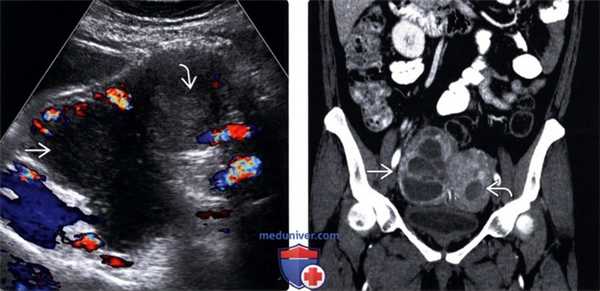

(Слева) Трансабдоминальная цветовая ультрасонография таза; определяется правый тубоовариальный абсцесс (ТОА) после расширения и выскабливания. В абсцессе отсутствует центральный цветовой поток. Эндометрий также утолщен.

(Справа) КТ с контрастированием, коронарный срез у той же пациентки; определяется распространение ТОА. Также визуализируется гиподенсивный эндометрий.